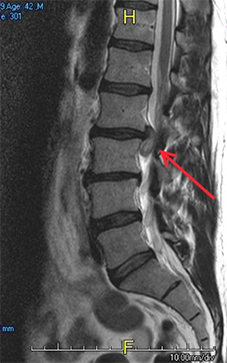

1.1: Vista de Perfil de la columna lumbar, se observa una hernia discal L2-L3.

El disco se encuentra situado entre dos vértebras y su función es de amortiguación, este disco a medida que pasa el tiempo va envejeciendo y perdiendo hidratación, elasticidad y altura, cuando la persona presenta una discopatía por degeneración de éste, puede sentir dolor durante semanas y meses que le impide realizar sus actividades habituales.